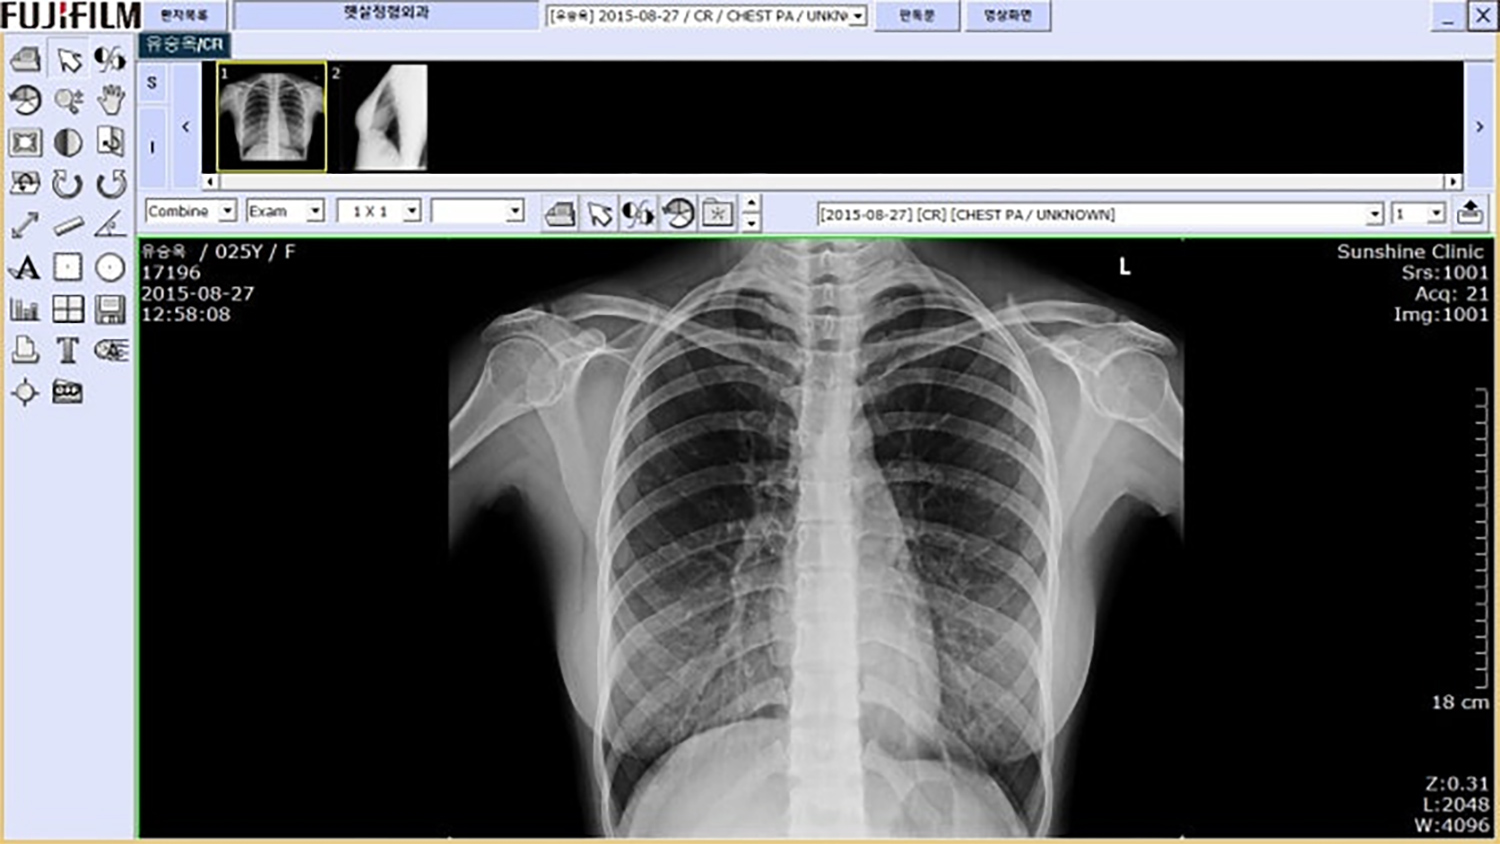

모델 유승옥 역시 지난 2015년 다큐멘터리 출연 이후 불거진 가슴 수술 의혹에 대해 적극적인 해명을 내놓았다. 당시 방송 화면에 포착된 겨드랑이 부근의 자국이 수술 흉터라는 주장이 온라인 커뮤니티를 중심으로 확산됐다. 유승옥은 근거 없는 추측이 이어지자 직접 병원을 방문하여 정밀 검사를 받는 결단을 내렸다.

그녀는 가슴 부위의 엑스레이와 CT 촬영을 진행하여 보형물이 삽입되지 않았음을 공식적으로 확인받았다. 유승옥 측은 보형물 미삽입에 대한 의사 진단서와 촬영 원본 데이터를 함께 공개하며 강력하게 대응했다. 논란의 중심에 섰던 흉터 의혹은 의학적 증거물들이 제시되면서 사실이 아닌 것으로 밝혀지며 일단락됐다.